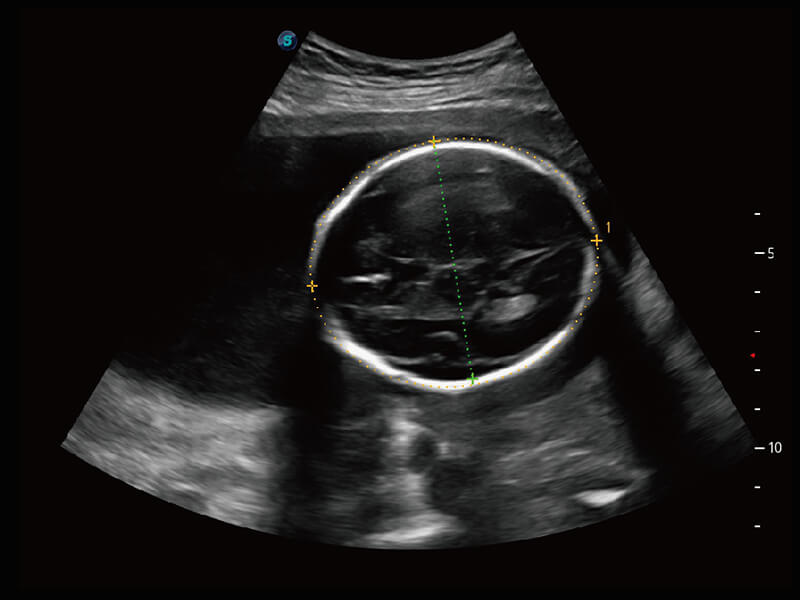

创新的超宽频带技术,为容积成像带来优质的二维图像基础,为您呈现更丰富的结构细节,栩栩如生地展示宝宝的宫内形态以及各种组织的立体结构。